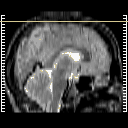

glioma overlay -- Slice #26

[Home][Help][Clinical] Slice 26